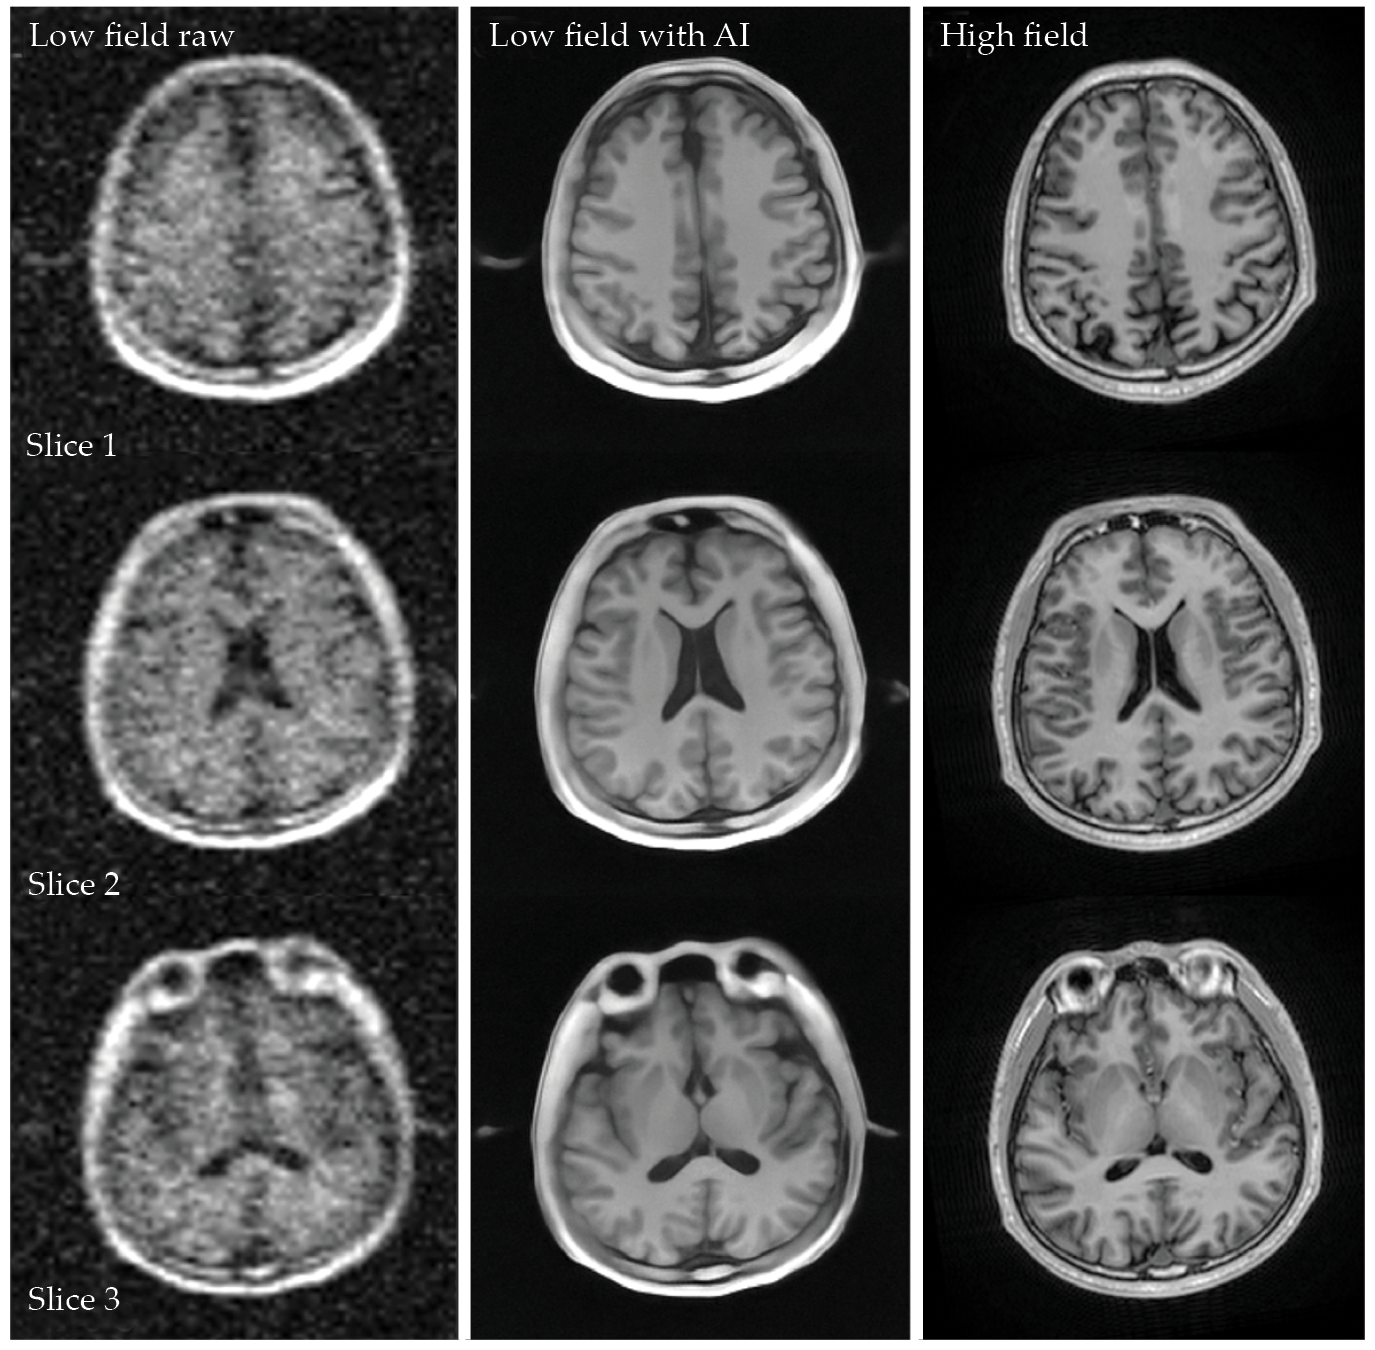

After training, Wu and colleagues’ AI model reduces noise artifacts in the low-field instrument’s images. Because the deep-learning algorithm is trained to identify the magnetic resonance signal, it can generate clean images even in a changing noise environment and without RF shielding. As shown in figure

Figure 2.

Artificial intelligence (AI) can reduce the noise and improve the spatial resolution of MRI. The left column shows image slices of a healthy human brain collected by a prototype 0.05 T scanner. The middle column shows the same images corrected with an AI deep-learning algorithm, and the right column shows results from a conventional 3 T scanner. Although some details are sharper in the high-field instrument’s images, the AI-reconstructed images show many of the same anatomical features. (Adapted from ref.

Although the new results are improved, the low-field images and the high-field images do have differences—as seen, for example, in some of the smaller, darker features at the edge of the brain in figure